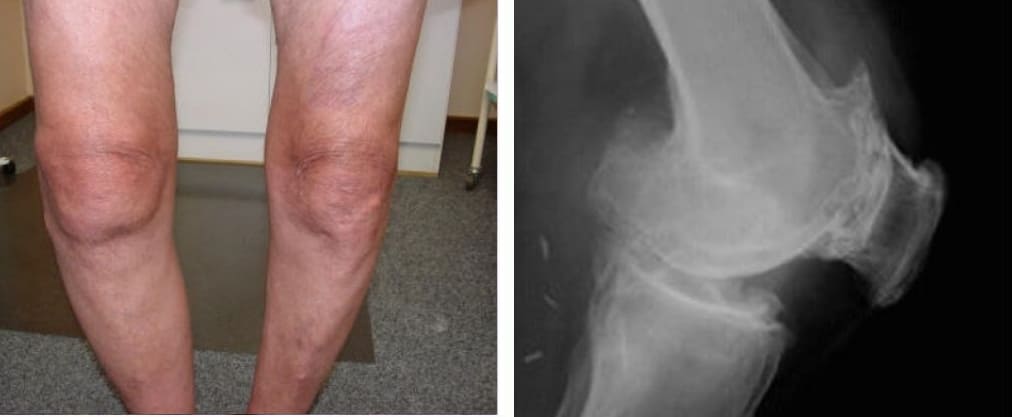

Atrofia y fuerte curvatura de las articulaciones de las rodillas, dolor constante y agudo incluso con los movimientos más leves.

Atrofia del cartílago de la rodilla, necrosis del tejido, destrucción completa de la articulación e inevitable amputación.